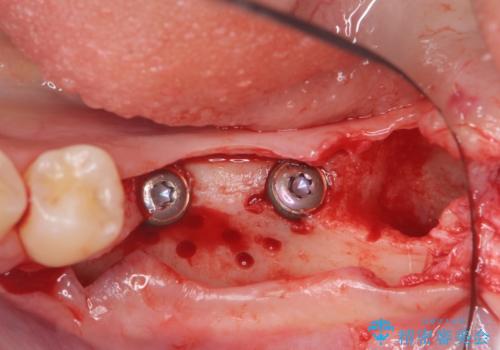

- 他院で抜歯後放置してしまった左下の奥歯の機能・見た目の回復を希望され来院されました。

放置したことによる影響か骨が吸収し、インプラント周囲に十分な骨が確保できないような状況であったため骨造成を併用したインプラント治療を計画します。

インプラントを用いて機能回復を行うことで、奥歯がしっかりと噛めるようになります。

周囲に骨があることでより長期的な予後を見込むことができます。